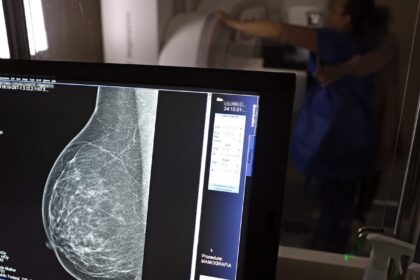

Câncer de mama: uma em cada três pacientes tem menos de 50 anos

Dados do Painel Oncologia Brasil, analisados pelo Colégio Brasileiro de Radiologia e…